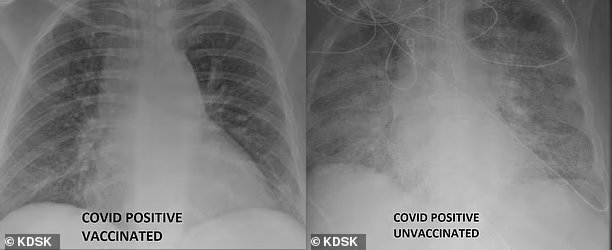

백신 접종한 코로나19 확진자의 폐(왼쪽)와 비접종 확진자의 폐(오른쪽)가 보인 엑스레이(X-Ray). 미국 방송국 KDSK

2일(현지시간) 영국 매체 데일리메일에 따르면 미국 미주리주 세인트루이스대학병원 특수치료시설(ICU) 소속 가산 카멜 박사는 코로나19 백신을 맞지 않은 채 확진된 환자와 맞은 채 돌파 감염된 환자의 폐를 비교했다.

깨끗한 모습을 보인 백신 접종한 환자의 폐(왼쪽)에 비해 뿌옇게 나타난 비접종 환자(오른쪽)의 폐. 미국 방송국 KDSK

카멜 박사는 현지 언론과의 인터뷰에서 “백신이 만들어내는 차이를 보여주기 위해 이 엑스레이 사진들을 공개했다”며 “백신 접종을 하지 않은 코로나19 환자는 약물치료와 인공호흡기, 호흡을 위한 삽관 등 생명유지 장치를 필요로 할 수 있다”고 설명했다.